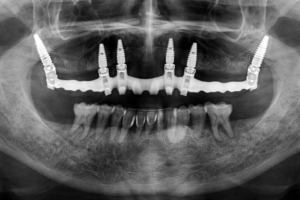

Fullarch / prótesis híbrida

¡Volver a sonreír con tranquilidad! Eso es el Full Arch. Queremos devolver a nuestros pacientes la funcionalidad y la estética en su sonrisa. Por eso, usamos esta maravillosa técnica quirúrgica, que permite reponer todos los dientes, sea arcada superior, inferior, o ambas, con el uso de implantes dentales, junto con una prótesis dental completamente fija, que se comporta como dentadura natural.